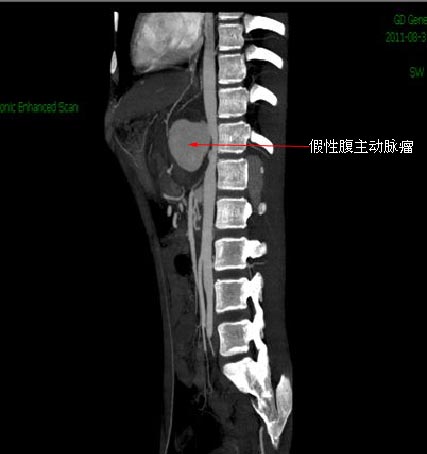

因动脉瘤长在肾动脉、肠系膜上动脉和腹腔干周围,这里都属手术禁区。在介入治疗中发现,双侧肾动脉以上2cm处见腹主动脉假性瘤扩张,直径约6cm,左侧副肾动脉水平见一夹层(血管内壁破损,血液入内壁形成囊疱)征象,夹层延续到髂总动脉分叉水平。